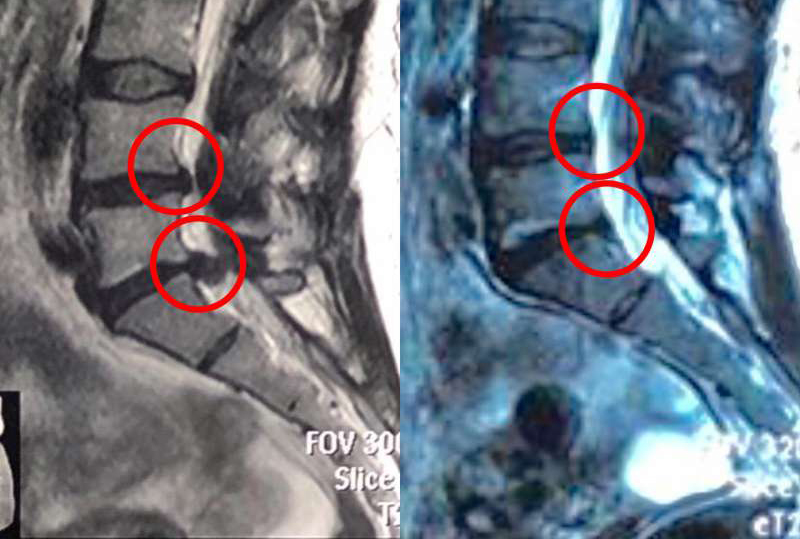

Резорбция межпозвонковой грыжи

Резорбция межпозвонковой грыжи – это комплекс мероприятий, направленных на уменьшение объема образования вплоть до полного его рассасывания. Процедуры стимулируют работу иммунных клеток организма, разрушение патологически измененных тканей и их реорганизацию с последующим рубцеванием. Комплексное воздействие способствует ускорению этих процессов.

Иммунитет воспринимает компоненты грыжи как чужеродный объект и запускает активные воспалительные процессы. Структуры постепенно пронизываются кровеносными сосудами, что позволяет иммунным клеткам работать более активно. Постепенно клетки грыжи разрушаются, ткани реорганизуются, поврежденное фиброзное кольцо замещается рубцовой тканью. Патологическое образование исчезает или значительно уменьшается в размерах. Если грамотно влиять на эти процессы, подстегивая, а не тормозя их, можно добиться впечатляющих результатов без применения хирургических технологий.

Результаты до и после